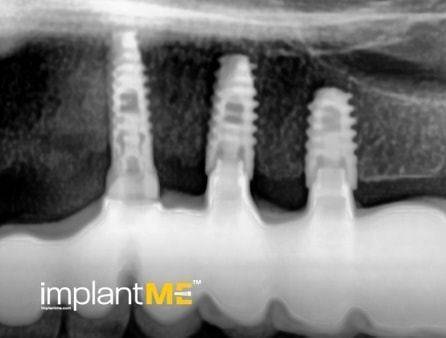

Τα ελκυστικά και ιδιαίτερα υγιή δόντια δεν είναι μόνο καθοριστικό μέρος της εμφάνισής μας, αλλά και της προσωπικότητάς μας. Παλαιότερα, η απώλεια ενός ή περισσοτέρων δοντιών είχε καθοριστικό αντίκτυπο στον τρόπο εμφάνισης των ανθρώπων. Λόγω της σύγχρονης στοματικής εμφυτευματολογίας, αυτό δεν συμβαίνει πλέον. Με συγκριτικά μικρές χειρουργικές επεμβάσεις από το στόμα, μεμονωμένα ή όλα τα ελλείποντα δόντια μπορούν να αντικατασταθούν από εμφυτεύματα, αισθητικά και λειτουργικά ίσα με τα φυσικά δόντια. Μέσω της εισαγωγής εμφυτευμάτων που σχηματίζονται σε ρίζα, είναι δυνατόν να αποφευχθούν αλλοιώσεις των γειτονικών δοντιών και να αγκυρωθούν στεφάνες που δύσκολα διακρίνονται από τα πραγματικά δόντια στα κενά των δοντιών. Οι στεφάνες ή οι γέφυρες που υποστηρίζονται από εμφύτευμα στερεώνονται στα εμφυτεύματα που είναι αγκυροβολημένα στο οστό, γεγονός που δίνει στους ασθενείς μια αίσθηση μάσησης σχεδόν διακριτή από τα δόντια τους. Σε περίπτωση πλήρους έλλειψης δοντιών, τα εμφυτεύματα μπορούν να παρέχουν αξιόπιστες αγκυρώσεις για αφαιρούμενα προσθετικά καθώς και για μεγάλες σταθερές γέφυρες.

Τα οδοντικά προσθετικά που υποστηρίζονται από εμφύτευμα βρίσκονται όσο πιο κοντά μπορείτε να φτάσετε στα φυσικά δόντια. Τα στεφάνια των εμφυτευμάτων βαθμολογούνται με τη φυσική τους εμφάνιση, τα εμφυτεύματα με τη σταθερότητα τους και και τα δύο με τη θετική τους επίδραση στη λειτουργική συντήρηση ολόκληρης της μαστιχικής συσκευής.